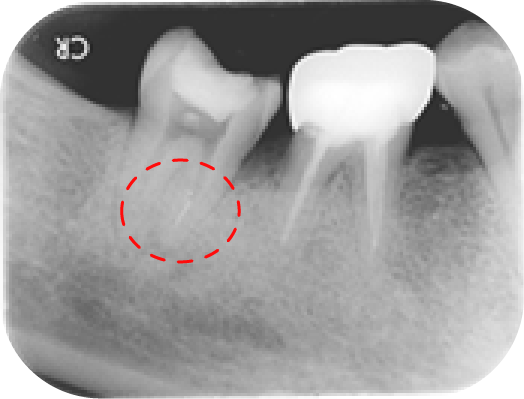

病人因其他院所醫師無法定位根管位置被轉診,在顯微鏡底下可以發現短短不到兩毫米的距離藏有兩根根管(圖中紅線標示處),這是傳統根管治療很難發現的。